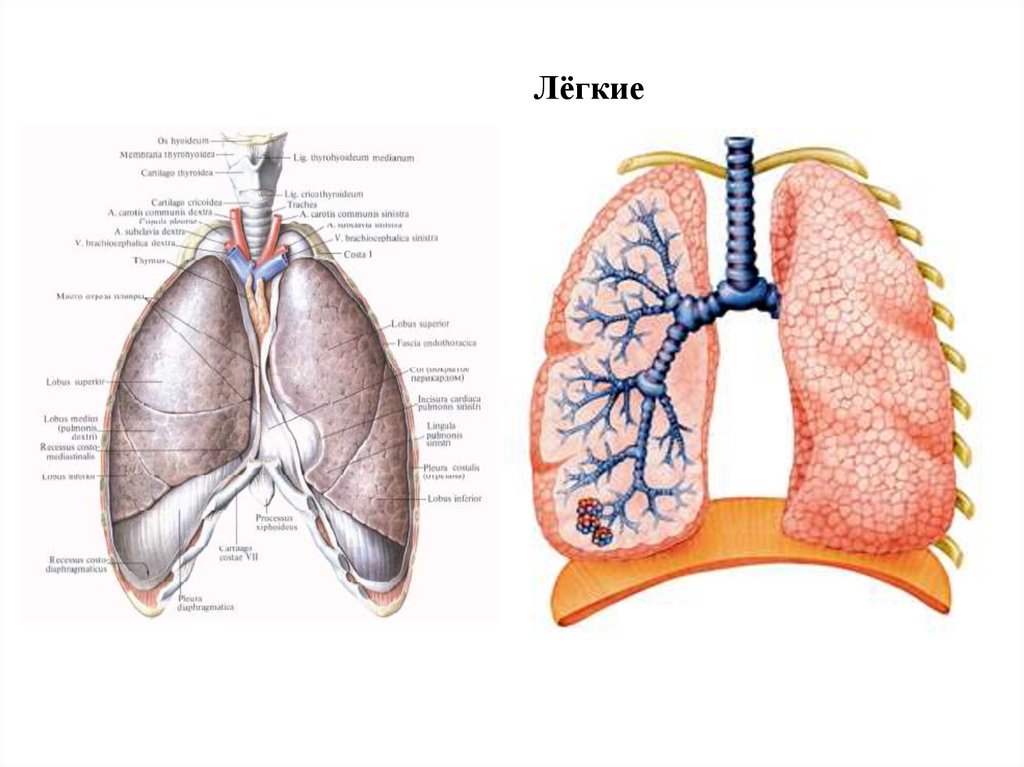

Схемы дыхания: Пневмоторакс на изображениях